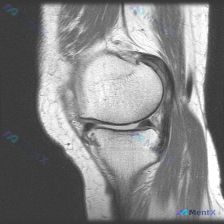

刚整理了一个很有临床意义的病例,核心矛盾是「临床怀疑软骨异常,但现有影像完全正常」,把整个分析思路分享给大家。 病例基础信息 这是一份单张膝关节矢状位T1加权MRI影像,临床提出的核心观察方向是「软骨异常」,无其他临床病史、症状或其他检查资料。 影像具体观察结果 我们先把影像所见说清楚: 1. 骨骼...

看到这个病例挺有代表性的,整理出来和大家分享一下思路。 病例基础信息 这是一张膝关节矢状位T1加权序列MRI影像,用户提出问题:观察图像是否存在软骨异常。 先给大家整理影像评估的基本结果: 1. 骨骼结构:股骨远端、胫骨近端、髌骨皮质连续,骨髓信号未见异常高低信号,关节面形态基本正常 2. 半月板:...

最近遇到一个挺有启发的读片问题,整理出来和大家分享一下: 病例基本情况 这是一份膝关节矢状位T1加权序列MRI,有人提出这份影像可以观察到「软骨异常」,我们先来看详细的影像分析结果: 影像结构整体评估 1. 骨骼结构:股骨远端、胫骨近端、髌骨骨皮质连续,无骨折;骨髓信号正常,无异常低信号提示水肿或占...

病例基础信息 这是一份特殊的膝关节影像评估需求:输入描述提示存在软骨异常 (Chondral abnormality),提供1张膝关节矢状位MRI静态图像,我们先看影像学分析结果: 影像学观察结果 1. 骨骼与软骨:股骨远端、胫骨近端、髌骨骨皮质完整,无骨折,无骨髓水肿;股骨髁、胫骨平台、髌股关节面...